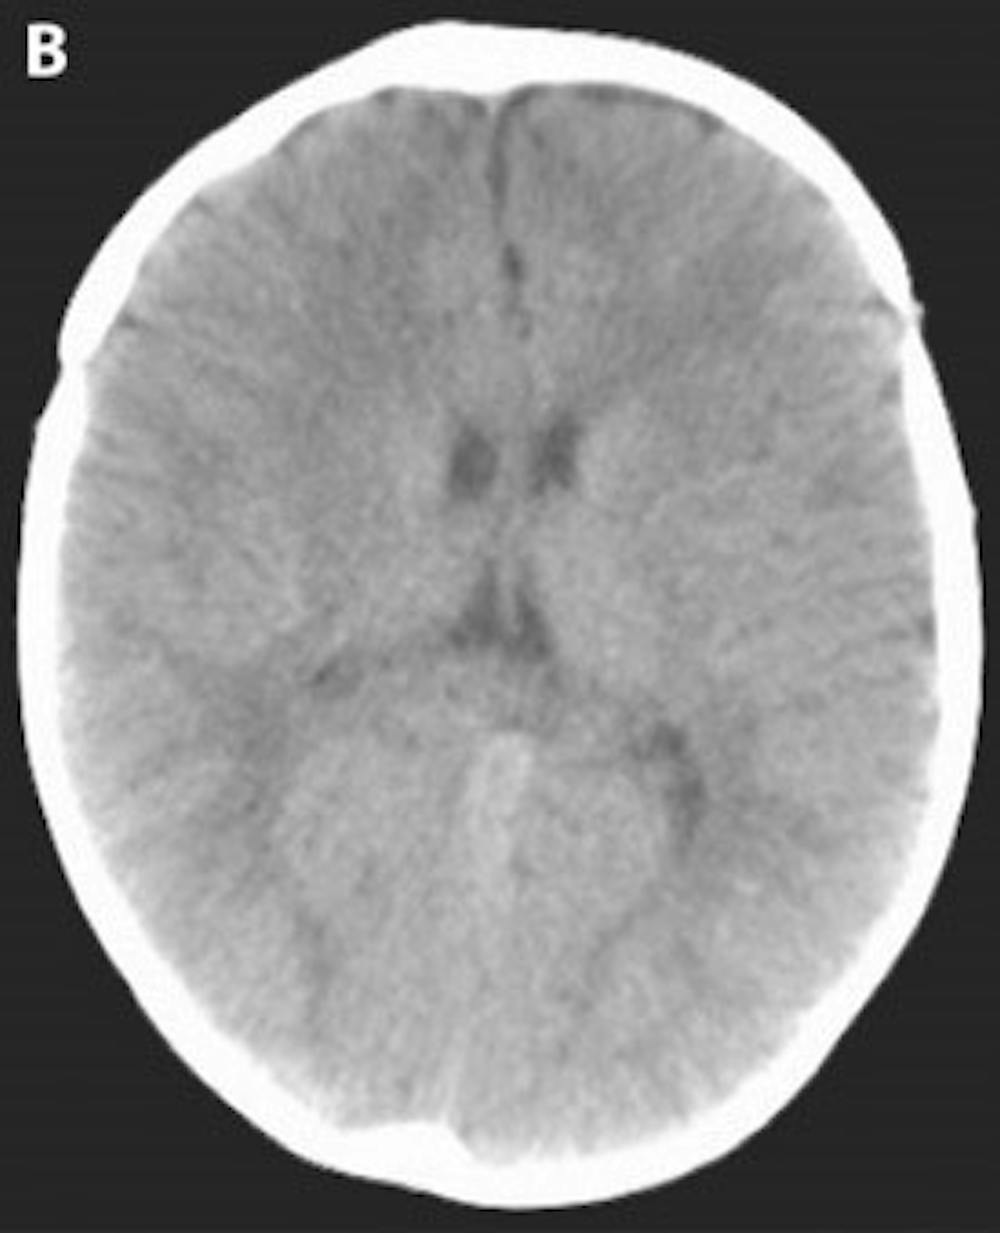

B) Post-operative head CT demonstrating a more cosmetically normal, rounded appearance to the skull